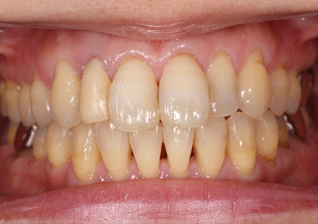

インプラントブリッジのジルコニアオールセラミックにて前歯部・審美領域の治療

- 主訴

- 事故で前歯を喪失、見た目と噛み合わせを治したい

- 治療内容

- 上顎前歯2本のインプラントと右上の天然歯を、同時に色調を合わせて修復を行なった

- 治療費用

- インプラントに関わる治療費:1,025,000円(税別)

- 治療期間

- 5ヶ月